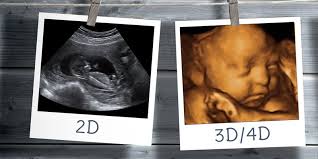

A 4D ultrahang a modern képalkotó technológia egyik leglátványosabb vívmánya, amely lehetővé teszi, hogy a kismamák és családtagjaik valós időben, mozgás közben lássák a magzatot a méhen belül. A 4D kifejezés arra utal, hogy a háromdimenziós (3D) képalkotást egy negyedik dimenzió, az idő egészíti ki, így a magzat nemcsak térben, hanem mozgásában is megfigyelhető.

A vizsgálat során részletes képet kapunk a baba arcvonásairól, testfelépítéséről és mozgásáról, például ásításról, mosolyszerű mimikáról vagy kéz- és lábmozgásokról. Ez az élmény sok szülő számára különösen meghatározó, hiszen segít még szorosabb érzelmi kapcsolat kialakításában a születendő gyermekkel. A 4D ultrahang elsősorban élményvizsgálat, ugyanakkor fontos kiegészítője lehet a hagyományos 2D ultrahangnak. A mozgó, térbeli képek segítségével bizonyos fejlődési sajátosságok és külső jegyek is jobban megfigyelhetők, például az arc, a végtagok vagy a gerinc alakulása.